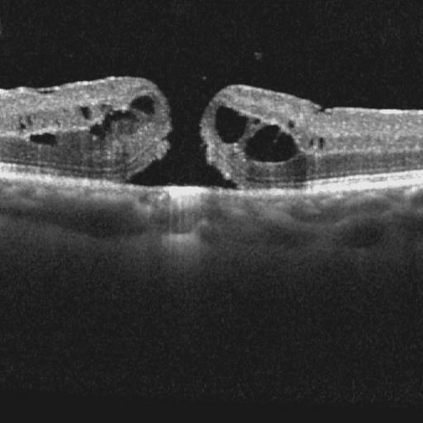

Ophthalmology relies heavily on detailed image analysis for diagnosis and treatment planning. While large vision-language models (LVLMs) have shown promise in understanding complex visual information, their performance on ophthalmology images remains underexplored. We introduce LMOD, a dataset and benchmark for evaluating LVLMs on ophthalmology images, covering anatomical understanding, diagnostic analysis, and demographic extraction. LMODincludes 21,993 images spanning optical coherence tomography, scanning laser ophthalmoscopy, eye photos, surgical scenes, and color fundus photographs. We benchmark 13 state-of-the-art LVLMs and find that they are far from perfect for comprehending ophthalmology images. Models struggle with diagnostic analysis and demographic extraction, reveal weaknesses in spatial reasoning, diagnostic analysis, handling out-of-domain queries, and safeguards for handling biomarkers of ophthalmology images.